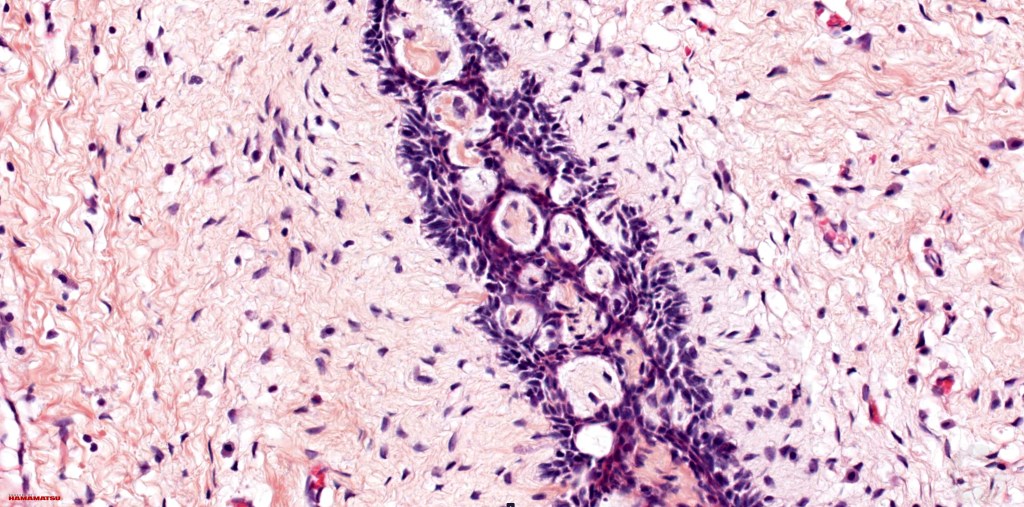

•Anastomosing basaloid, narrow epithelial strands associated with a prominent fibrous (sometimes myxoid) stroma

•Ductal differentiation likely represents entrapped ducts rather than spread along the eccrine ducts

•Peripheral palisade

•Round to oval vesicular nuclei with small nucleoli

•Occasional cysts